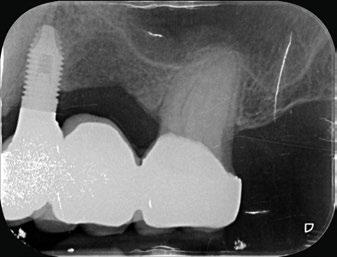

directamente a cabeza de implante para realizar una prótesis dentoalveolar de cerámica de 3 piezas, que equilibraran la oclusión y dieran soporte al labio y la mejilla (Figuras 14-17)

Figura 14. Imagen intraoral frontal postoperatoria al año de la reconstrucción.

Figura 15. Detalle de prótesis dentoalveolar cerámica en visión lateral.

Figura 16. Ortopantomografía postoperatoria.

Figura 17. Resultado final.